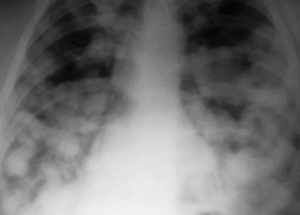

В феврале 2022 г. кашель усилился, появились фебрильная температура тела, одышка, пациентка была госпитализирована с диагнозом “новая коронавирусная инфекция COVID-19 (вирус идентифицирован), двусторонняя полисегментарная пневмония (КТ-2)”; проводилась терапия левилимабом согласно клиническим рекомендациям.

На компьютерных томограммах (КТ) органов грудной клетки (ОГК) от 20.02.2022 в обоих легких визуализировались участки по типу “матового стекла”, ретикулярные изменения, зоны консолидации, с поражением 45-50% в правом легком, 35% - в левом легком (рис. 1).